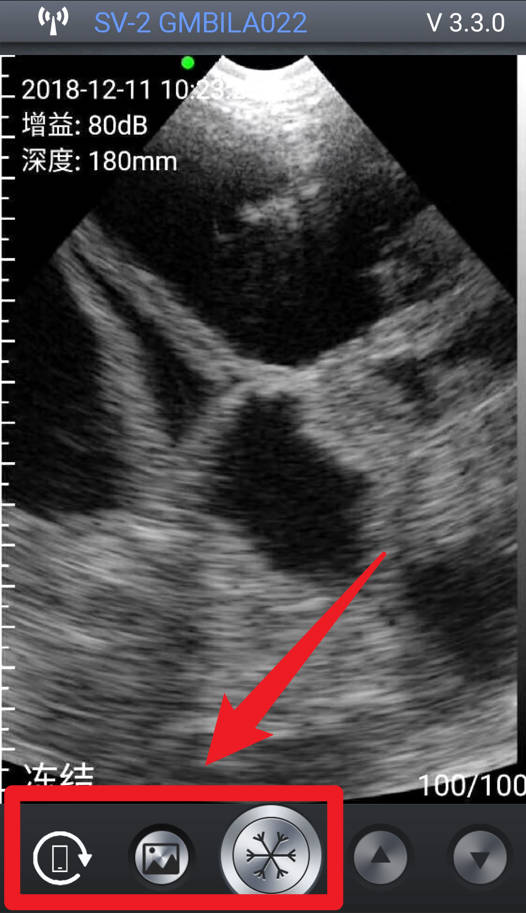

1、在进入APP后,屏幕左上角会显示当前时间、深度参数,若设备未连接或未启动探头,这些值将显示为--。

2、点击手机旋转图标,即可进行屏幕旋转控制,适应横屏或竖屏查看,提高操作便捷性。

3、当探头正常工作且图像实时显示时,界面左上角会显示具体的增益,用户可据此调整图像清晰度与探测深度。